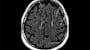

A validation study has shown that a new artificial intelligence (AI)-based image analysis tool, iQ-Solutions MS Report (IQ-MS; SNAC, Camperdown, Australia), significantly outperforms standard radiology reports in detecting multiple sclerosis (MS) disease activity in real-world clinical settings.

Investigators found that IQ-MS more sensitively detected new or enlarging brain lesions associated with MS (93.3%) compared to standard clinical radiology reports (58.3%), with only a minor drop in specificity (97.6% vs. 98.8%). The AI tool also showed equivalence with a core clinical trial imaging lab in measuring lesion activity and brain volume loss (93.3% vs. 85.0%).